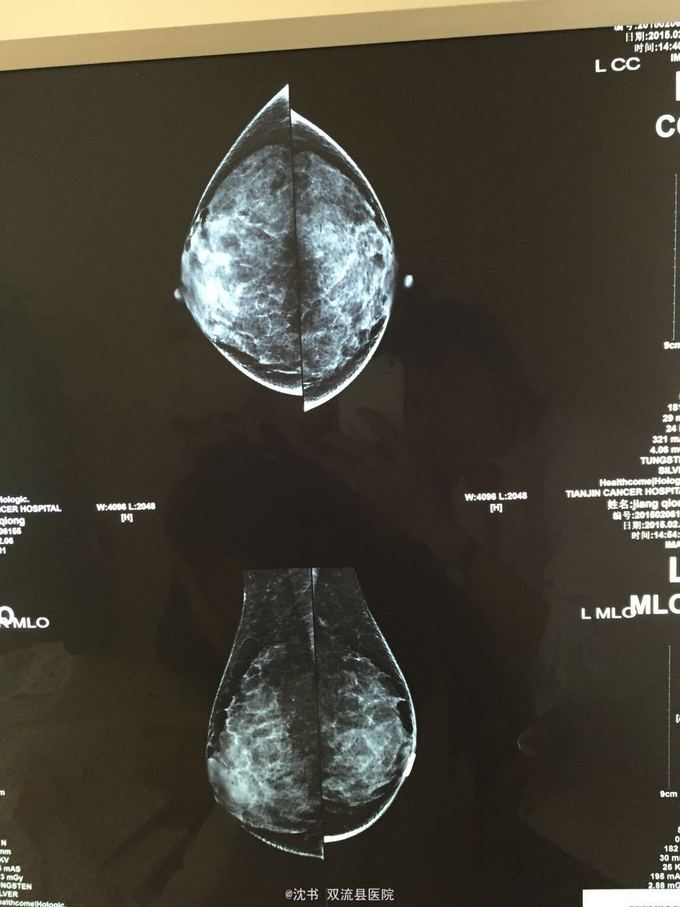

查体:双乳对称,右乳后方空虚感,右乳11点触及一韧结节,右乳头外上边缘少许灰白色液,左乳无溢液。双腋可触及2-3cm韧厚块。 外院彩超:双乳增生伴囊肿 外X线:右乳乳晕后方不规则团块影:炎症?左乳外上结构紊乱。

诊断:1、右乳11点结节:炎性结节?2、右乳溢液:原因待查。3、双乳囊肿 处理:双乳彩超+右乳溢液涂片+右乳11点结节穿刺活检。